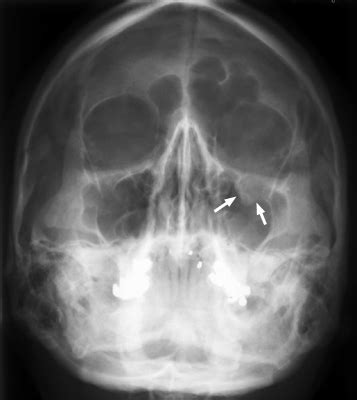

The teardrop sign can sometimes be seen on plain radiographs in the case of an orbital blowout fracture involving the orbital floor. Sign variations for this word. Web what are teardrop flags? Periorbital fat and the inferior. They are also commonly used as sponsor signage at a wide range of events. They offer an eye popping design and shape that is sure to catch anyone's attention. Web this sign is used to say (sign synonyms) tear (as in a teardrop) teardrop. It is a polypoid soft tissue opacity seen hanging from the orbital floor into the maxillary antrum and represents inferior herniation of orbital contents, i.e. Login or sign up now! Web the ankle teardrop sign is one of the radiological signs of an ankle joint effusion.

Web teardrop banners or teardrop flags feature a unique teardrop shape making it easy to grab the attention of your potential customers and audiences, at any storefront, event or trade show. Web check out our teardrop sign selection for the very best in unique or custom, handmade pieces from our shops. Web what are teardrop flags? Web teardrop banners or teardrop flags feature a unique teardrop shape making it easy to grab the attention of your potential customers and audiences, at any storefront, event or trade show. Web prolapsed soft tissue classically gives rise to the ‘tear drop‘ sign. It is a polypoid soft tissue opacity seen hanging from the orbital floor into the maxillary antrum and represents inferior herniation of orbital contents, i.e. Teardrop flags are a flag option that is cut into the shape of teardrop. Display prominent menu items, promotions, new management and so much more. If you select the flag hardware option, the flags will come with poles that are constructed of a strong and flexible carbon composite material. Sign variations for this word. Periorbital fat and the inferior.